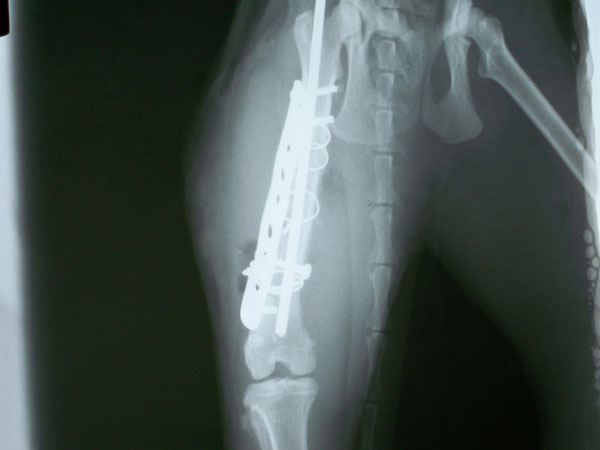

Οι ακτινογραφίες είναι πρίν και μετά το χειρουργείο.

Ενα απόλλυμα συγκρατήθηκε στο περιφερικό τμήμα με συμπιεστικό κοχλία και μεταλλικό ράμμα περιμετρικά του οστού.

Τοποθετήθηκε ενδομυελικός ήλος Retrograde για την ανάταξη και το κεντρικό τμήμα συγκρατήθηκε με μεταλλικό ράμμα.

Επ'ισης τοποθετήθηκαν δύο ακόμα μεταλλικά ράμματα και brighting plate με δύο διφλοιικούς κοχλίες στο περιφερικό τμήμα

και ένας μονοφλοιικός κοχλίας στο κεντρικό τμήμα.